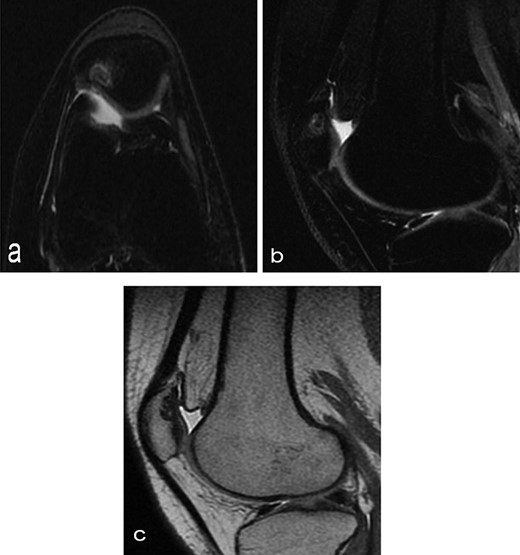

A 14-year-old female dancer presented with increasing right knee pain and functional disability without any trauma. Her pain was retropatellar pain that often radiated medially or laterally from the patella, exacerbated by climbing stairs, running and squatting. She was unable to perform any sports activities. Examination revealed peripatellar tenderness and crepitus, full range of motion and the knee was stable. Radiological examination included both MRI and computed tomography of the knee were performed at the beginning. MRI showed osteochondritis dissecans at the area at the superolateral facet of the patella in the deep subchondral area as shown in Fig. 1. This was appropriately treated conservatively with 6 months of reduced load and protected weight bearing without relief of symptoms. She quit sport activity for 2 years and then another MRI was performed Fig. 2. After 2 years we opted for adipose-derived mesenchymal stromal cells (AD-MSCs) intra-articular therapy according to the procedure described by Tremolada et al. [9]. The patient’s parents were given written information regarding the use of AD-MSCs therapy, including relative risks of this therapy and also relevant treatment alternatives that could otherwise be explored. Postoperative radiological evaluation was performed at 6 months and 12 months after AD-MSCs procedure as shown in Figs. 3 and 4. Postoperative clinical evaluation was performed using IDKC, Lysholm and Tegner scores (Table 1). After surgery, patients began a McConnell program of lateral retinacular stretching, patellar taping and vastus medialis obliquus muscle exercises. The patient was encouraged to swim and cycle to reduce impact loading. Using AD-MSC, she reported a complete relief of pain after 1 year from the procedure. Routine MRI follow-up 2 years later showed evidence of appreciable improvement in cartilage volume and osteochondral architecture at the site of injury. Early MRI T2 mapping at 6 months indicated that the area of cartilage regeneration exhibited high water content suggestive of immature cartilage or fibrocartilage morphology. Later T2 mapping at 18 months after the procedure, indicated progressive maturation of cartilage from deep to superficial layers with more hyaline like cartilage morphology. Limitations of the study are lack of arthroscopic intra-articular visualization and classification of the patella lesion.

Twelve months after MSC treatment in (a) axial and (b) sagital T2-weighted of MRI T2 sequences the OCD in patella showed that area was almost regenerated with good fibrocartilage morphology.